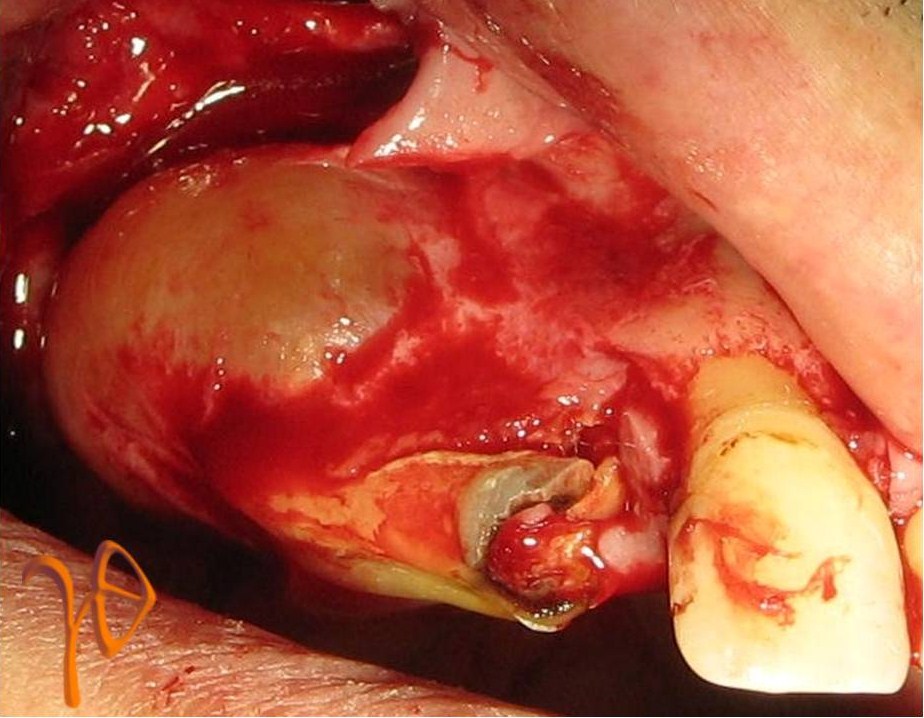

Μια άλλη περιοχή του στόματος που μπορεί να δέχεται μακροχρόνιο ερεθισμό είναι ο βλεννογόνος των φατνιακών αποφύσεων, δηλαδή τα νωδά ούλα που στηρίζουν τις ολικές οδοντοστοιχίες. Η αντιδραστική βλάβη που μπορεί έτσι να εκδηλωθεί ονομάζεται ινώδης πτυχωτή υπερπλασία (Εικόνα 8).

Εικόνα 8. α. Περίπτωση κάτω δεξιάς αντιδραστικής υπερπλασίας (βέλος) – στο ένθετο η βλάβη παρασκευασμένη πριν την αφαίρεση, β. Άλλη περίπτωση κάτω αριστερής αντιδραστικής υπερπλασίας.